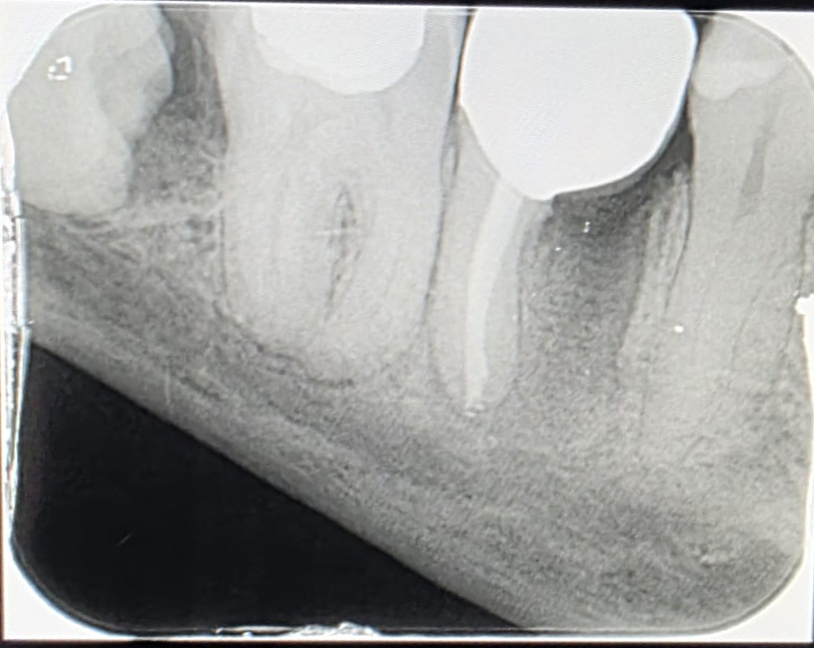

Meğer dişte üç kök varmış. Aletin kırıldığı ve yanındaki küçük kökün bulunduğu taraf kesilip çekilecek, kalan büyük kök üzerine kaplama yapılacakmış. Dişin yarısını doğal bir implant gibi düşünün. İmplant yaptıranlar sürecin ne kadar rahatsızlık verici olduğunu bilirler. Maddi karşılığından bahsetmiyorum bile. Neyse, diş filmini de aşağıda paylaşıyorum; içerideki kırık aleti net şekilde görebilirsiniz.